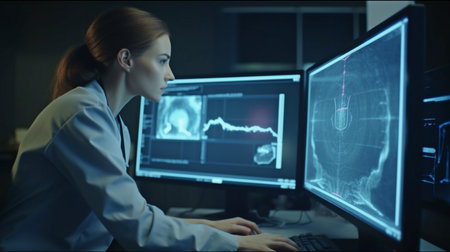

veterinarian doctor with MRI computer control

veterinarian doctor working in MRI scanner room